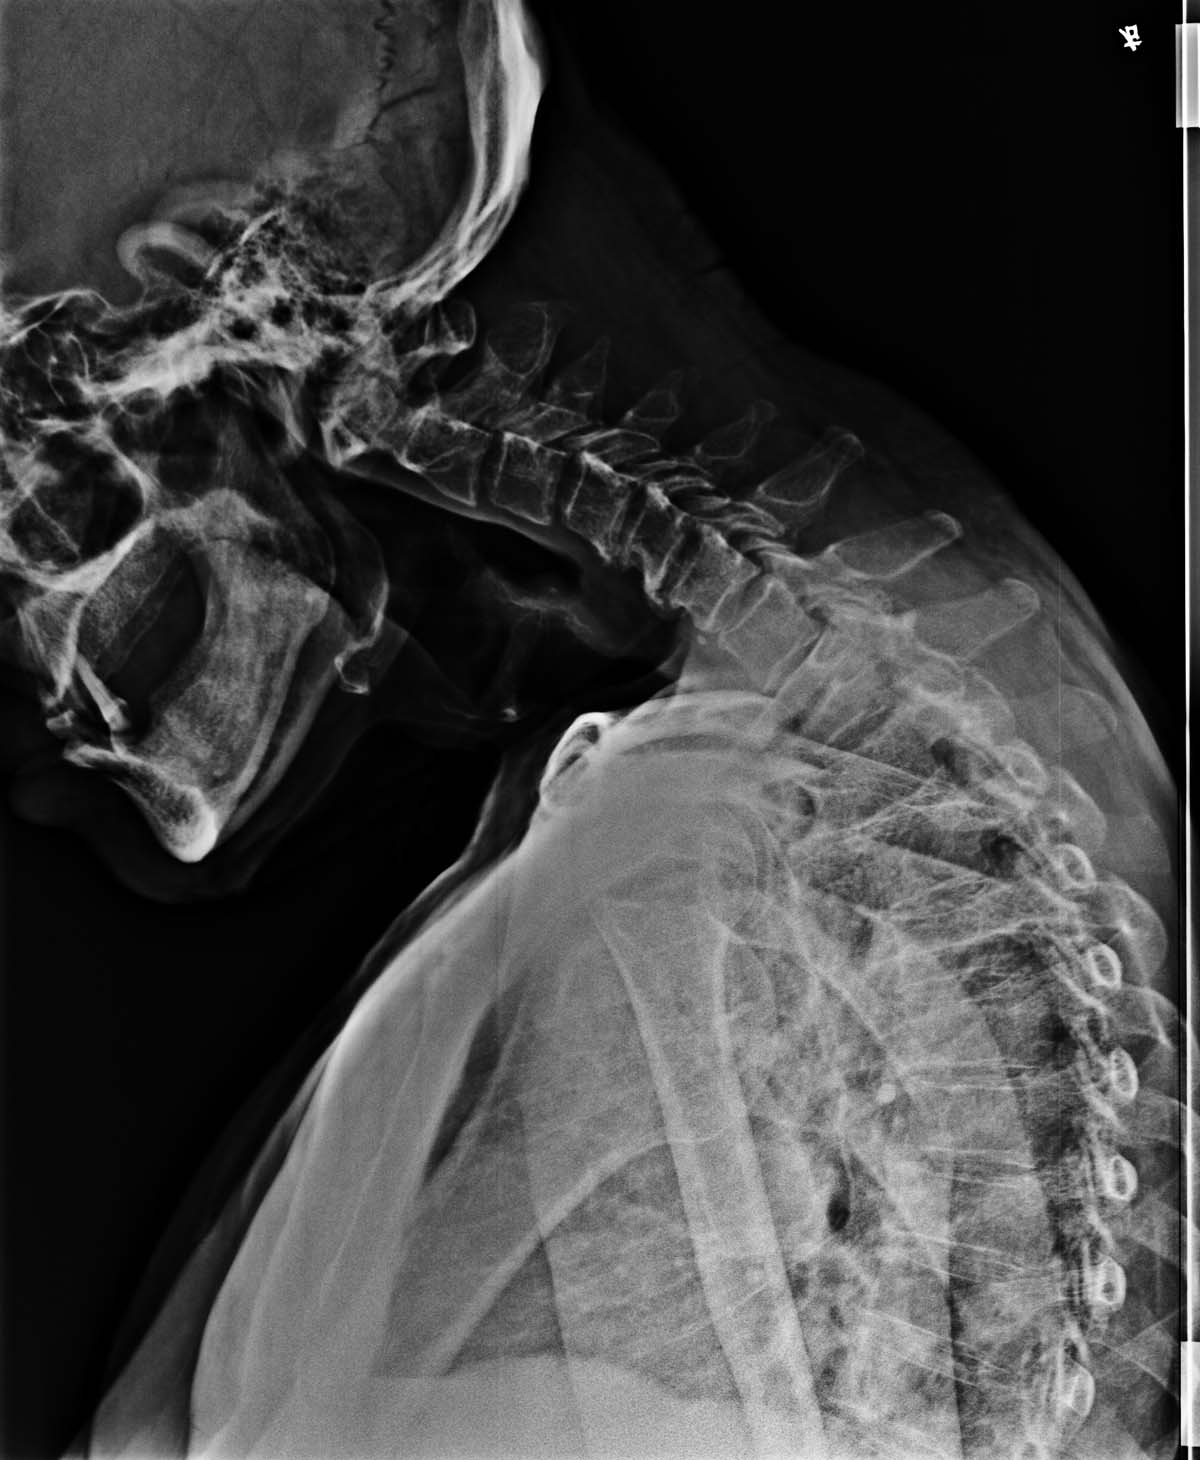

男,85岁,头一直进行性往下低,请教各位老师,这是脊椎什么病因。

1、考虑退行性变,毕竟85了,肌肉无力了

2、加照腰骶椎片,除外强直性脊柱炎。

补充说明:腰椎及胸椎显示未见明显强直性脊柱炎改变,双侧骶髂关节间隙正常,未见异常。强直性脊柱炎上行性已排除。

颈前肌萎缩。